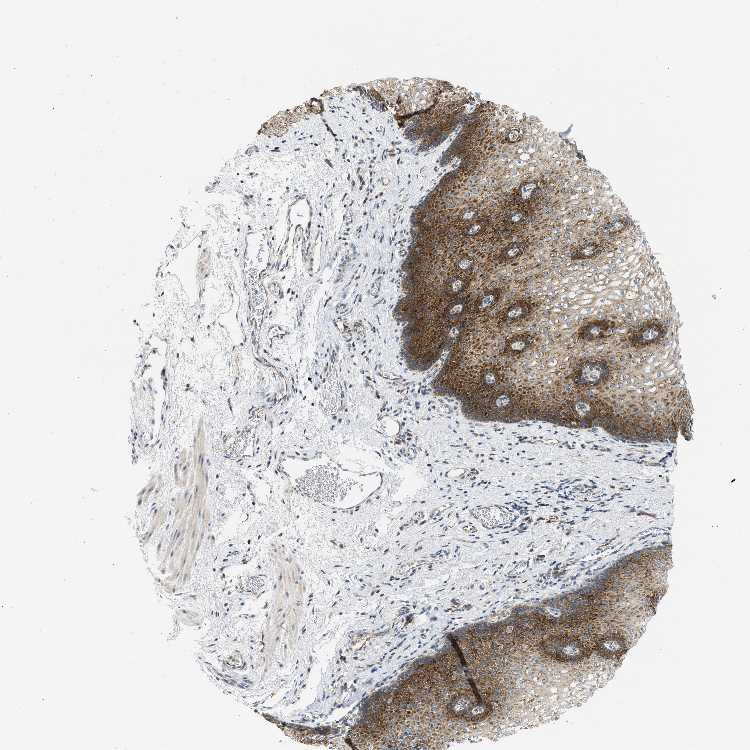

ESOPHAGUS - Antibody stainingi

Antibody staining in the annotated cell types in the current human tissue is reported as not detected, low, medium, or high, based on conventional immunohistochemistry profiling in selected tissues. This score is based on the combination of the staining intensity and fraction of stained cells.

Each image is clickable and will lead to virtual microscopy that enables deeper exploration of all samples and also displays staining intensity scores, fraction scores and subcellular localization as well as patient and tissue information for each sample.

Antibody HPA017389Antibody HPA063713

Squamous epithelial cells HighNot detected